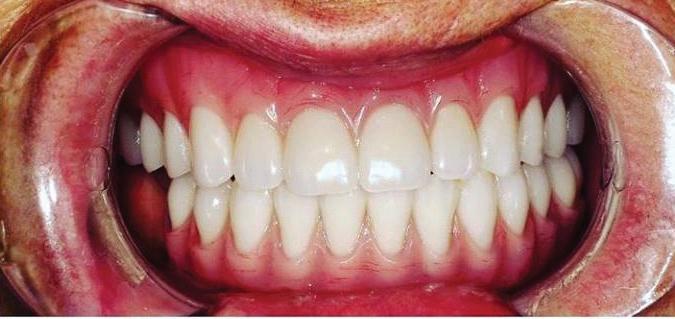

Submitted By Sivakumar Sreenivasan, DMD, MDS Dental Implant Center of Rockville

Tooth loss is extremely common among adults, especially as we age. Rather than living with the discomfort and hassles of dentures, many people are opting for what is called “all-onfour” dental implant restoration.

An implant is a small titanium

screw that fits inside your jawbone and replaces the root-part of a missing tooth. Minor surgery is required to insert the implants. Once the implant is in place, a crown is attached to give you a highly realistic-looking and functional prosthetic tooth.

You do not need a dental implant for each and every one of your missing teeth. All you need is four precisely placed implants on the top of your mouth, and four on the bottom, to restore your full smile. That’s the beauty of the all-on-four. And because the implant is made of titanium, it has the unique ability to fuse to living bone and function as part of it. So eventually, the dental implant becomes part of the jawbone and serves as a strong, longlasting foundation for your new teeth.

Besides ensuring that your implants are permanently fixed in place, this bone fusion has another important benefit: it prevents future bone loss in the jaw. This helps to maintain a more youthful facial structure – and better